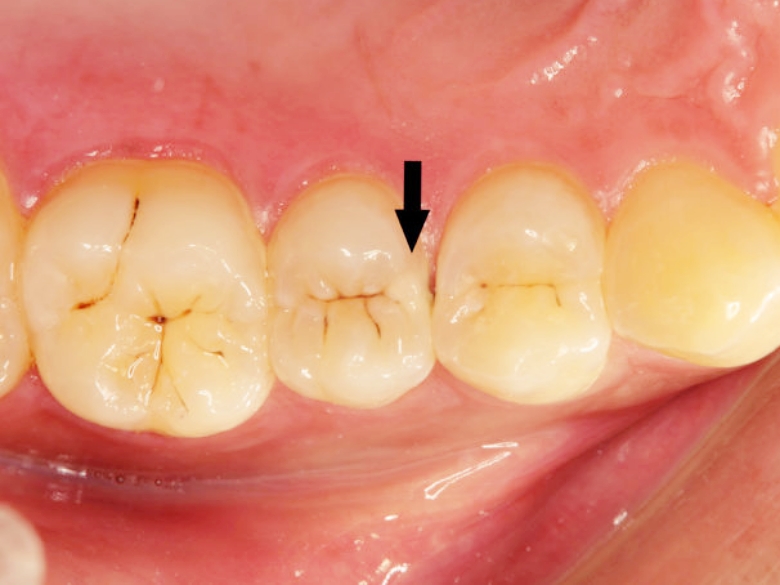

이 증상은 단순히 불편함으로 여겨지기 쉽지만, 그 원인은 생각보다 다양해요. 대개 잇몸이 내려가면서 치아의 뿌리 부분이 드러나며, 차가운 자극이 직접 전달될 때 갑자가 이가 시려요 라고 하실 수 있어요. 또, 치경부 마모증이라고 해서 잇몸이 내려간 부위의 치아와 잇몸 사이가 패이면서 시릴 수 있으며, 초기 충치 또는 충치가 깊어졌을 때 그쪽으로 달거나 짠 게 들어가는 것도 원인이 될 수 있죠.

시린 것 같기도 하고 아닌 것 같기도 하다면 양치를 잘 하시면서 상태를 지켜보다가 계속 반복되거나 증상이 심해졌을 때는 내원을 하시는 게 좋습니다. 정확한 진단을 위해서는 꼭 치과에서 사진을 찍고 확인하는 과정이 필요한데요. '시리긴 한데 치과 갈 정도는 아닌 것 같아요'라고 생각하실 수 있지만, 증상을 방치하게 되면 충치가 깊어지면서 결국 신경치료나 크라운 치료로 이어질 수 있어요.

지켜볼 수 있었던 증상이 당장 치료가 필요한 상태로 바뀔 수 있기 때문에 초기 충치 검사를 통해 증상 악화를 미리 방지하는 것이 가장 좋은 방법입니다. 그래도 혹시 시린 증상이 있으시다면, 아래 항목을 체크해 보세요.

갑자기 이가 시려요라고 하시며 방문하신 경우 우선 진료가 필요한 경우와 보존적으로 경과를 지켜볼 경우를 구분해, 가능한 덜 침습적인 방법을 우선 고려해요. 치경부 마모증이라면 그 부위가 계속 파이는 걸 막기 위해 GI(보험 진료용 재료)나 레진으로 치료하고, 잇몸이 내려갔다면 불소를 도포하거나 적응을 도와주는 약제를 사용해 볼 수 있어요. 심한 충치라면 그 상태에 맞는 방법을 선택하기도 하죠.